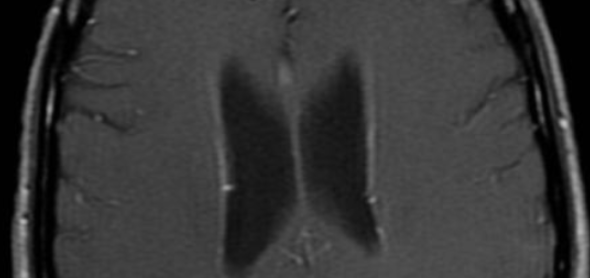

Encéphalite à VIH (HIV)

- Atrophie cérébrale++

- Leucopathie périventriculaire++ (épargne les fibres en U)

- Cliniquement : démence à HIV